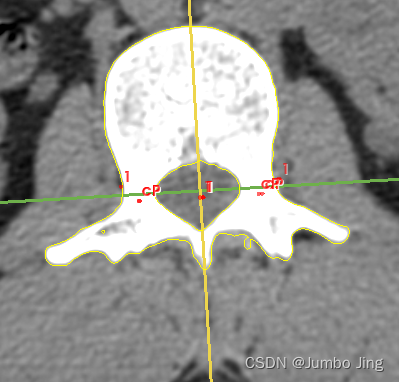

问题一:求当前截面椎弓根质心

问题二:求当前截面椎管的质心